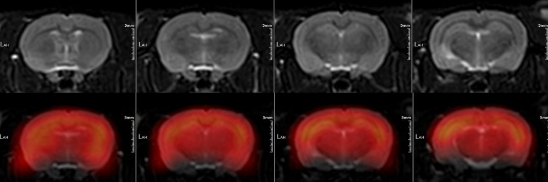

④轉化醫學研究也是PET / MR的重要應用場景。傳統小動物模型影像學研究主要使用小動物PET及小動物高場MRI,一體化PET / MR所具有的2.8mm的超高NEMA分辨率,以及動物線圈和PET衰減矯正算法、專為動物成像優化的MRI序列,使得臨床使用的PET / MR開展動物模型研究成為可能(圖5)。

圖5 一體化PET / MR業界最高空間分辨率配合動物專用協議與多尺寸組件,適應各種科研需求